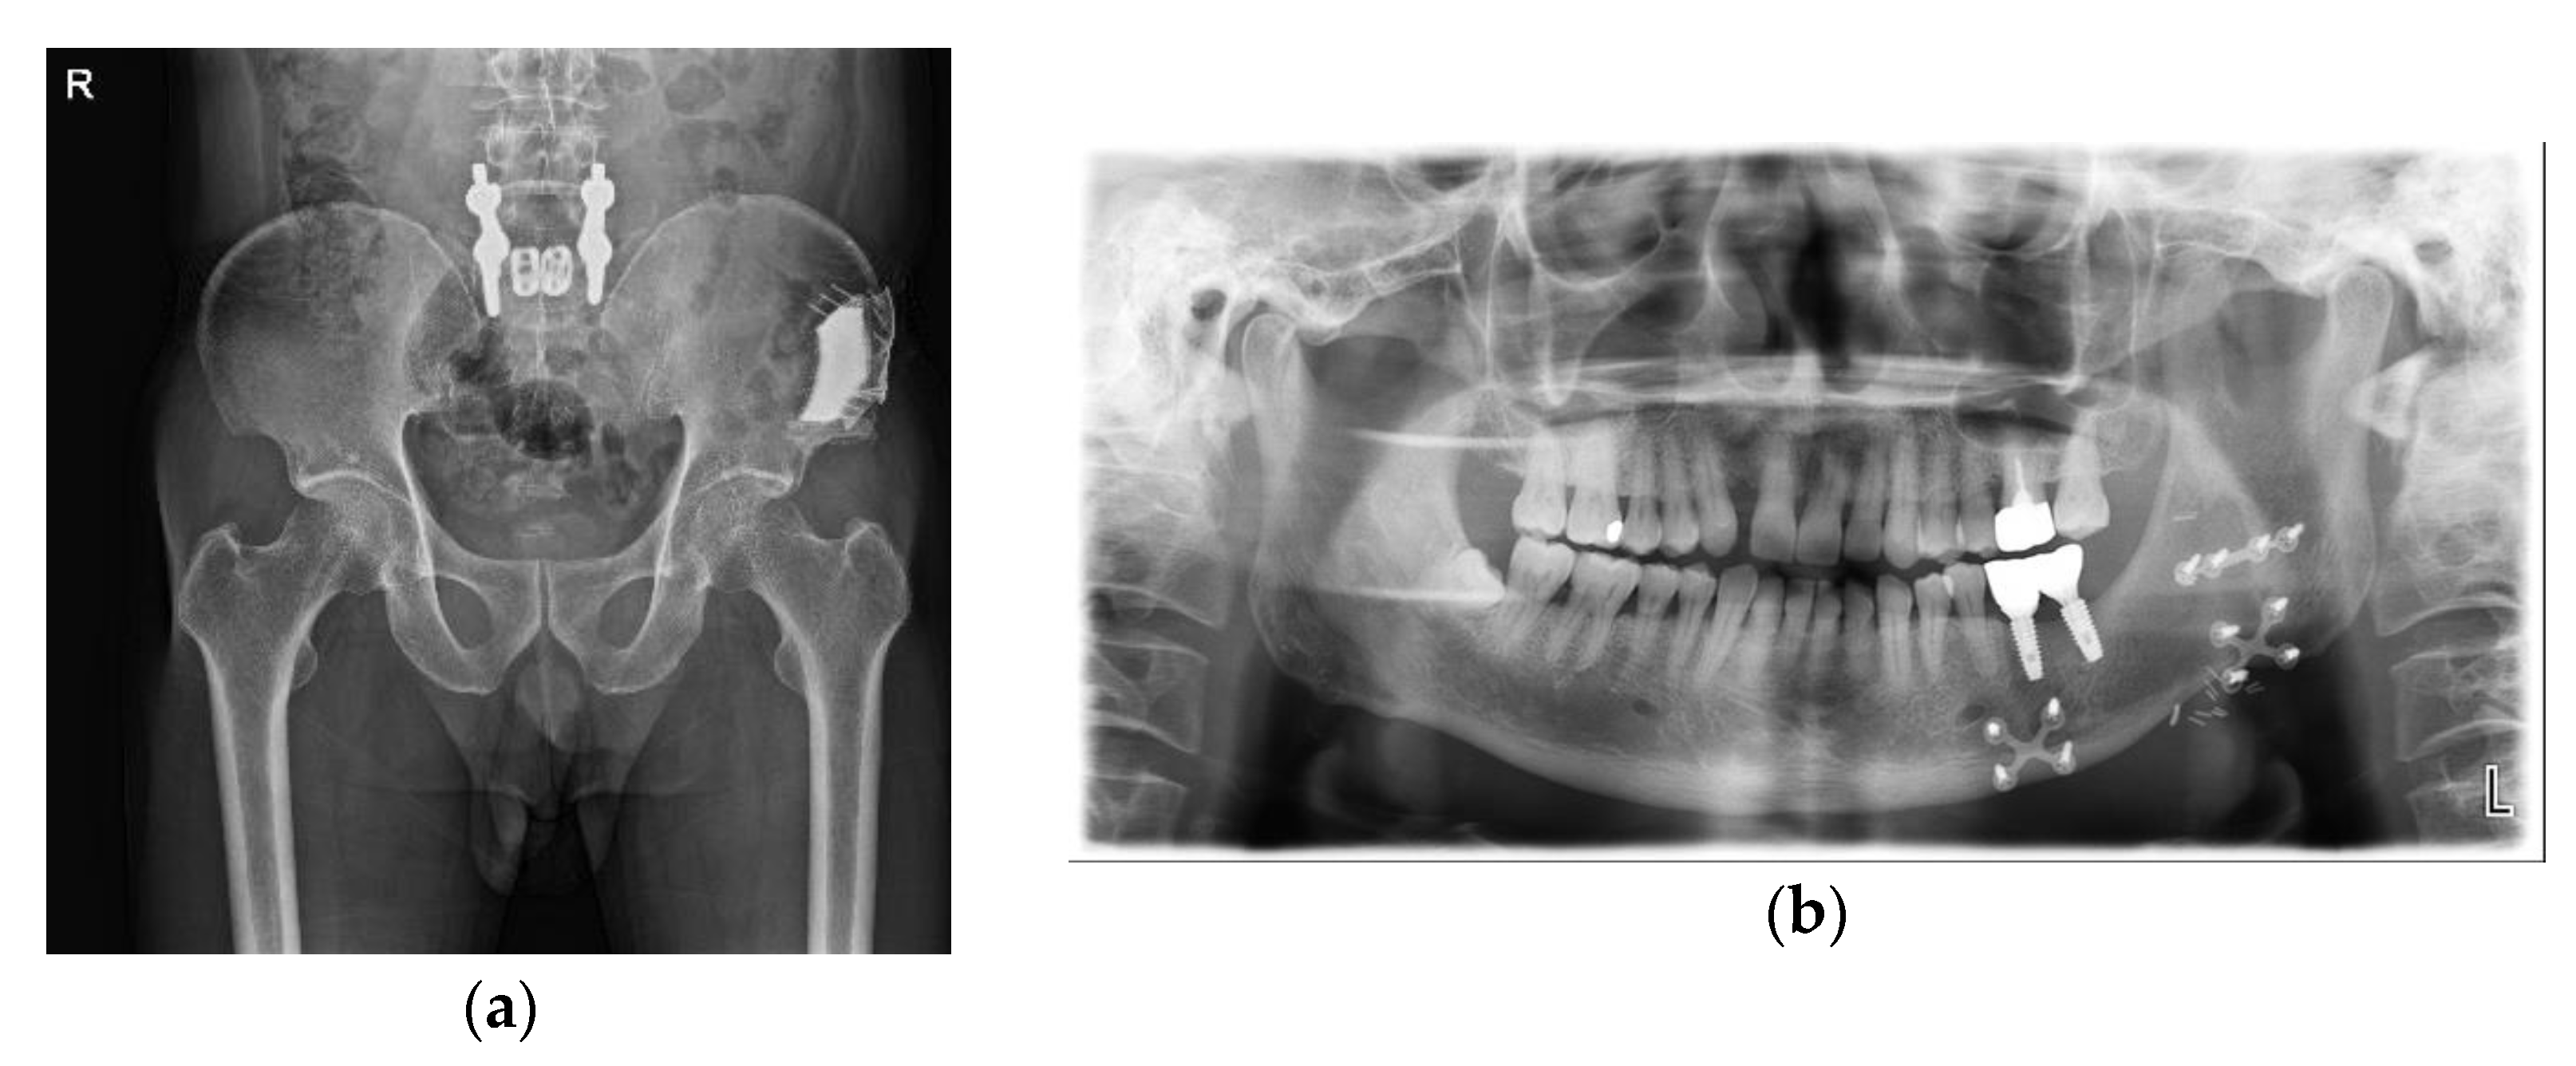

2.2.2. Surgical Technique

Conservative Treatment of Avulsion Fracture

3. Discussion